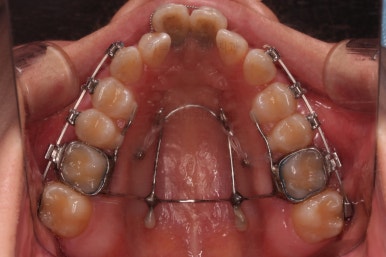

1. 초진

부산개방교합 키다리아저씨치과에 처음 내원 시 입안의 모습입니다.

전반적으로 치열이 삐뚤고요.

앞니쪽이 다물어지지 않는 개방교합(오픈바이트, open bite) 을 보였습니다.

어금니 맞물림을 보면 앵글씨 2급 부정교합 양상이어서 위아랫니가 모두 1대1로 부딪히고 있는 상태였습니다.

3. 치료과정

장치 부착은 윗니 어금니부터 했습니다.

미니스크류를 다양하게 활용하여 어금니 높이를 조절합니다.

여전히 앞니는 내버려둔 채로, 윗니는 어금니쪽만 진행하며 아랫니도 장치를 부착했습니다.

난이도가 매우 높은 치료인만큼 미니스크류의 구성과 장치 구성도 매우 복잡했는데요.

윗니 어금니를 뒤로 밀면서 앵글씨 2급 부정교합을 개선해 주고, 높낮이를 조절하면서 개방교합을 개선해 줍니다.